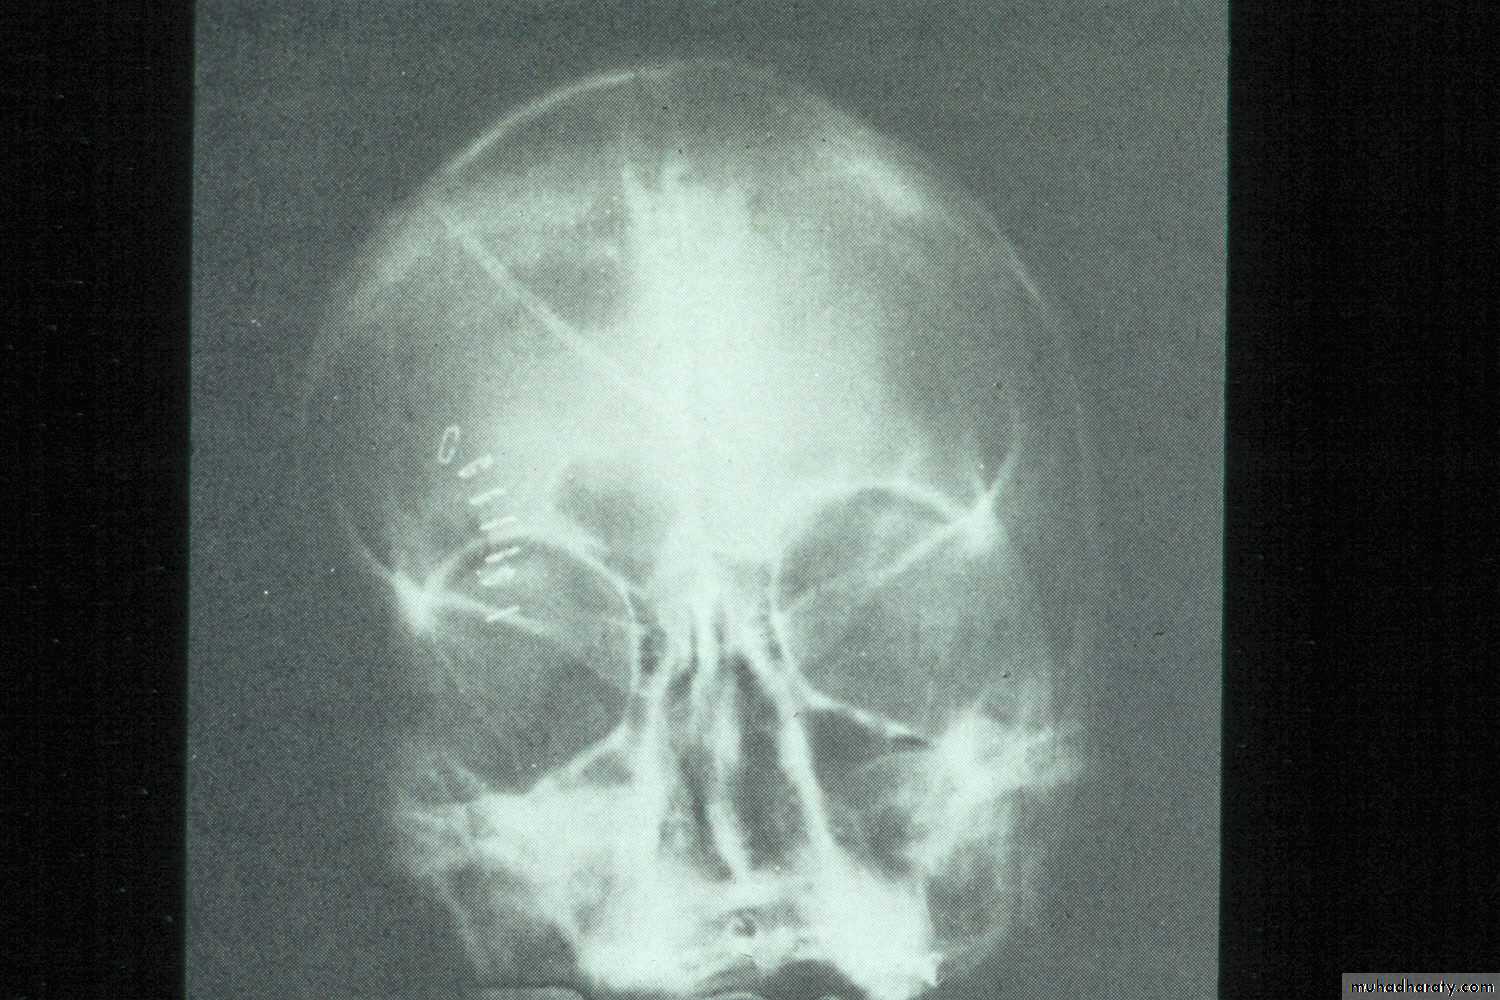

d. Occipitofrontal View: Is recommended to detect multisinusitis,

pansinusitis, if present.e. Tomography:This technique provides details of sinus structure.

Water’s view with air-fluid level in left maxillary sinus

Water’s view showing air-fluid level in right maxillary sinus and mucosal thickening in left maxillary sinus